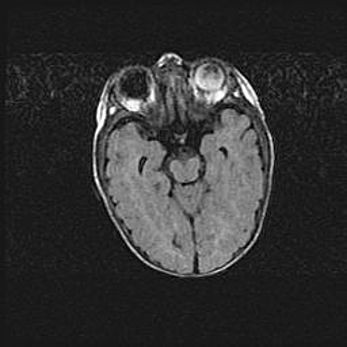

Мальформация Денди-Уокера. Киста задней черепной ямки.

Агенезия мозолистого тела.

Возраст: 2,5 месяца

Вес: 2420 г

Пол: женский

Окружность головы: 37 см

Срок гестации: 32 недели

Мальформация Денди—Уокера — редкий вид патологии ЦНС, представляющий собой врожденный порок развития каудального отдела ствола и червя мозжечка, ведущий к неполному раскрытию срединной (Мажанди) и латеральных (Лушка) апертур IV желудочка мозга. Для этогно синдрома характерна триада симптомов: гипотрофия червя мозжечка и/или полушарий мозжечка, кисты задней черепной ямки, гидроцефалия различной степени. В 70% случаев порок сочетается и с другими аномалиями головного мозга, в частности с агенезией мозолистого тела.